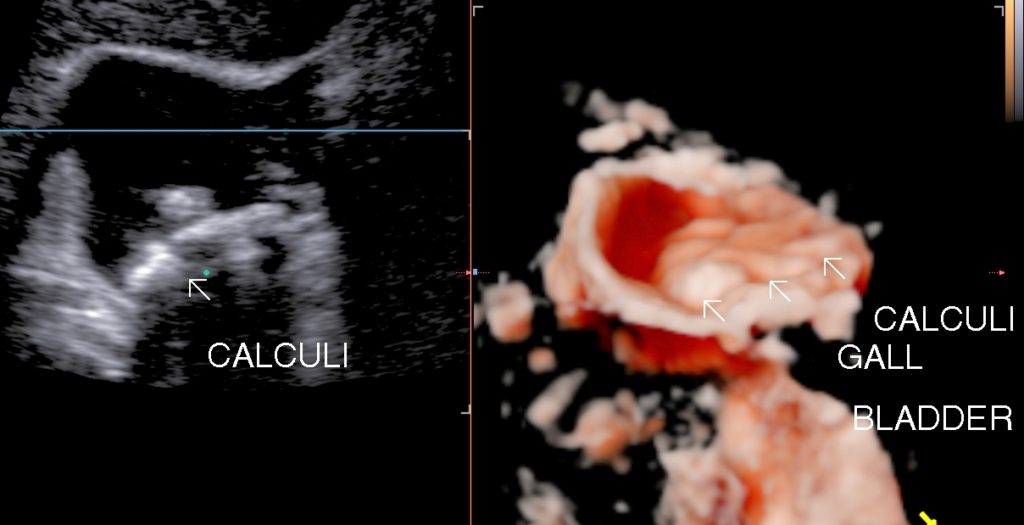

• Cholelithiasis: Presence of calculus/ calculi in gall bladder with normal wall thickness is known as cholelithiasis.

• Symptoms: Symptoms are right upper abdominal pain, dyspepsia, fullness of abdomen,bloating or may be asymptomatic. Impaction of calculi at neck or cystic duct leads to acute calculus cholecystitis. Passage of calculi in Common bile duct may lead to biliary colic , surgical jaundice & acute pancreatitis.

• Findings: Shows presence of calculi in gall bladder/ common bile duct, its mobility & complications.